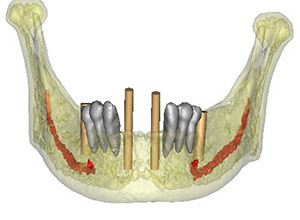

Este procedimiento requiere, en primer lugar, que tomemos los registros de la boca del paciente a través de una tomografía cone beam la cual se transfiere a el software que se encarga de proyectar la prótesis a través de la reproducción digital en 3D y obtener el mejor diagnóstico.

En el mismo software se realiza la planificación para la colocación de los implantes colocando virtualmente los implantes en la zona favorable y de esta manera se realiza una guía quirúrgica.